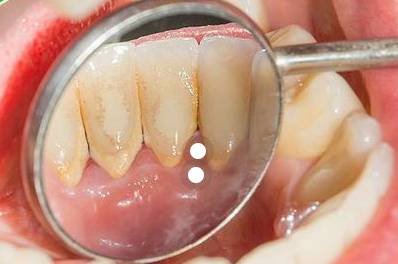

박테리아의 무색 필름인 플라그와 달리 치석은 미네랄이 쌓여 잇몸선 위에 있으면 쉽게 알 수 있습니다. 치석의 가장 흔한 징후는 치아나 잇몸의 노란색 또는 갈색입니다. 치석을 감지하고 제거하는 유일한 방법은 치과 의사나 치과 위생사를 만나는 것입니다.

잇몸선 위, 아래, 위에 형성되며 잇몸 조직을 자극할 수 있습니다. 치아의 치석은 플라그가 자라날 더 많은 표면적과 접착할 표면을 훨씬 더 많이 제공하기 때문에 충치와 잇몸 질환을 유발할 수 있습니다. 치석이 잇몸선 위로 모이면 조직이 부어오르고 쉽게 피가 날 수 있습니다. 이것은 치은염입니다.

치석은 또한 다공성이고 쉽게 얼룩을 흡수하기 때문에 미용상 문제가 될 수 있습니다. 따라서 커피나 차를 마시거나 흡연하는 경우 치석 축적을 예방하는 것이 더욱 중요합니다.